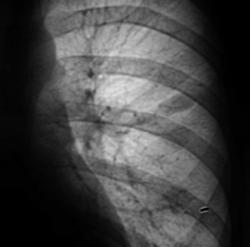

Глянули "архив", Оказывается в архиве есть флюорограммы за 2008 год.

Архив за 2007 год.

Мы посмотрели архив за 2007 год. Сейчас выложу.

Добавлены данные за 2007 год.

Я не думаю, что Вас "глючит", так как Вас просто "не может глючить". Я тогда, в 2007 году, "повязал" скиалогическую картину справа на уровне 1 ребра справа, и наличие овальной формы тени средней интенсивности слева в 3 межреберье. Один из наших уважаемых пользователей, сказал как-то, что я "постоянно заточен на туберкулёз", и это правильно, с учетом "нашей эпидситуации". Так вот тогда, я с большим скрипом и неудовольствием, высказался в пользу специфического процесса, хорошо понимая, что данных весьма мало.

А на боковой рентгенограмме, вроде-бы кропноочаговая тень не одна? А вроде-бы две?